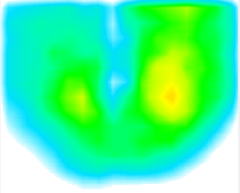

【2】リハビリ介入前

いつも通り座った状態です。右臀部に荷重が偏っていますが、患者さんにはその認識がありません。

【4】リハビリ介入後

リハビリ後、患者さんには画面を見せず体圧を計測。

左座骨部分への荷重量と左側への支持基底面積が増大し、体幹バランスが改善していることが確認できました。